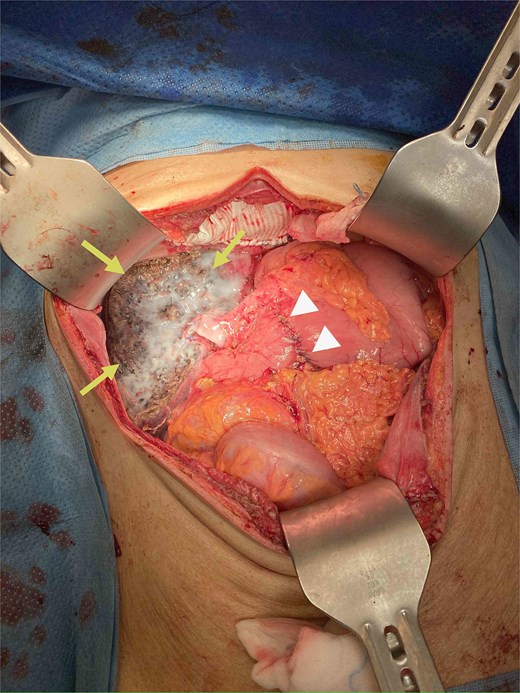

During operation, an exophytic 7 cm segment 4 tumor was found invading superiorly to left hemidiaphragm and pericardium, inferiorly invading to first part of duodenum. A cuff of duodenal wall was removed with tumor and the duodenal defect was closed primarily with 3/0 PDS. Part of the left hemidiaphragm together with pericardium was resected, the heart and left lung were exposed (Fig. 3). The diaphragmatic/pericardial defect was closed with Gore-Tex mesh with single layer continuous 3/0 Prolene (Fig. 4). Air was expelled through an under-water seal catheter placed in the pleural cavity before suture was tightened and tied. Left trisectionectomy was then completed (Fig. 5). The patient developed intra-abdominal collection after surgery which resolved with percutaneous drainage. Pathology confirmed a 7 cm ICC, there was evidence of rupture with abscess formation, and adhesion but no direct invasion to duodenum and diaphragm (Fig. 6). The resection margin was clear. No satellite lesion or microvascular invasion. CEA decreased to normal level after surgery. The patient declined adjuvant chemotherapy.

Specimen removed, the transected liver surface was covered with applied tissue glue (arrows) and the duodenal repair site was seen (arrow heads).